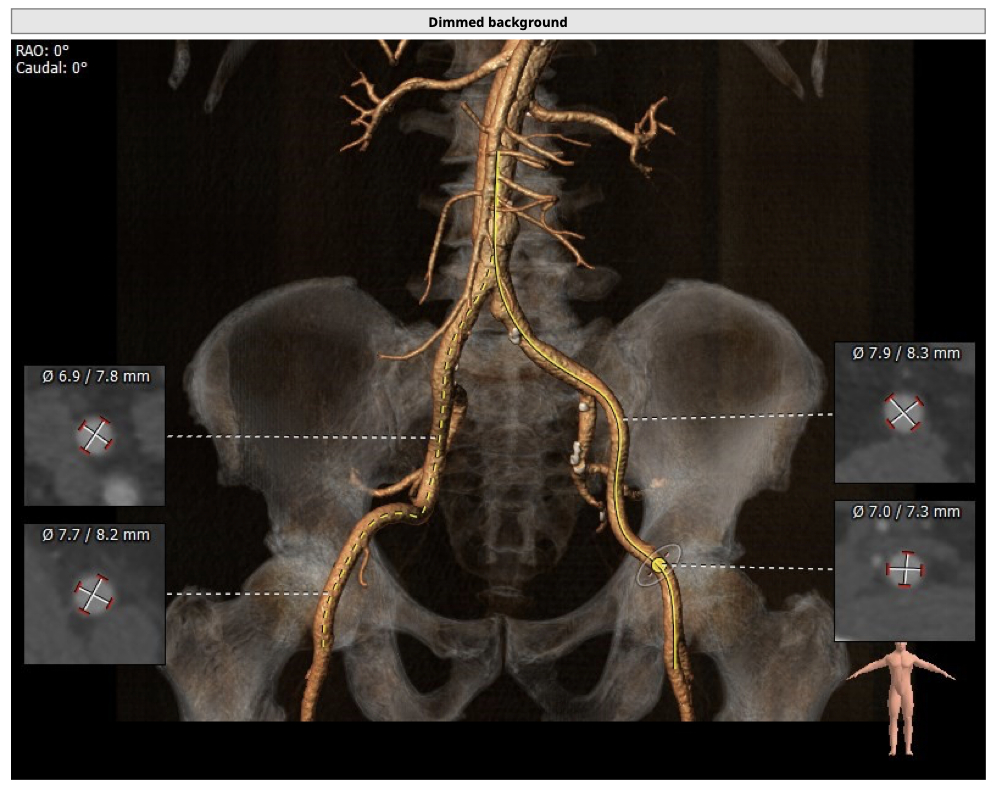

主动脉CT

患者为三叶瓣,轻度钙化,右无、左右疑似部分融合,左冠高度可,右冠高度高,法式窦结构大,左室大,升主动脉未见明显扩张,右股动脉可作为主入路。

经分析研判,根据患者的瓣环径,结合患者瓣上结构,优先选用L26号的VenusA-Valve瓣膜,备L29,使用22mm球囊预扩,根据球扩情况进一步确认选瓣,瓣膜释放后结合造影和超声情况,决定是否后扩。